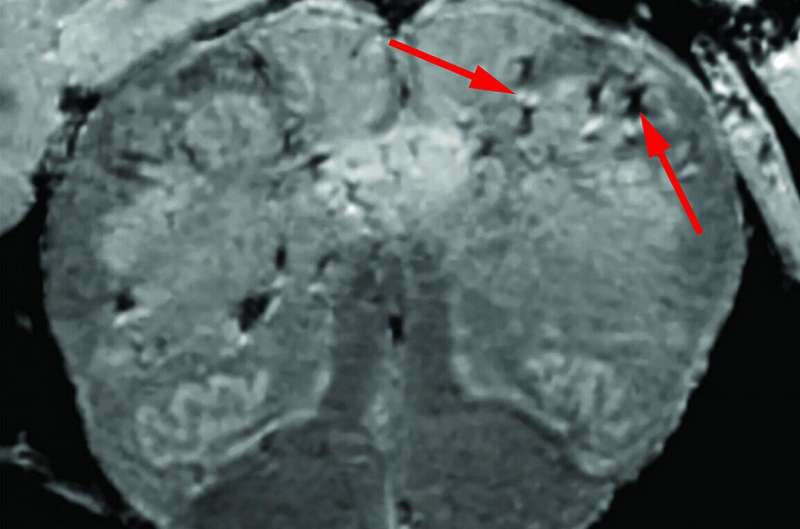

Sự xâm lấn thần kinh tổng quát hơn được tìm thấy trong cơ thể do viêm lan tỏa và thiếu máu cục bộ thứ phát sau tổn thương mạch máu.